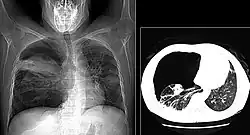

The diagnosis can be confirmed by the characteristic appearance of the chest X-ray and an arterial oxygen level (PaO2) that is strikingly lower than would be expected from symptoms. Gallium 67 scans are also useful in the diagnosis. They are abnormal in about 90% of cases and are often positive before the chest X-ray becomes abnormal. Chest X-ray typically shows widespread pulmonary infiltrates. CT scan may show pulmonary cysts (not to be confused with the cyst-forms of the pathogen).

-

Chest X-ray of increased opacification (whiteness) in the lower lungs. -

These chest radiographs are of two patients. Both show ground glass opacities. The left X-ray shows a much more subtle ground-glass appearance while the right X-ray shows a much more gross ground-glass appearance mimicking pulmonary edema.[7] -

X-ray of a cyst in pneumocystis pneumonia[7] -

High-resolution computed tomography (HRCT) showing ground-glass attenuation with a geographic or mosaic distribution.[7] -

HRCT of cysts of pneumocystis pneumonia. These are usually multiple and bilateral, but range in size, shape and distribution.[7]